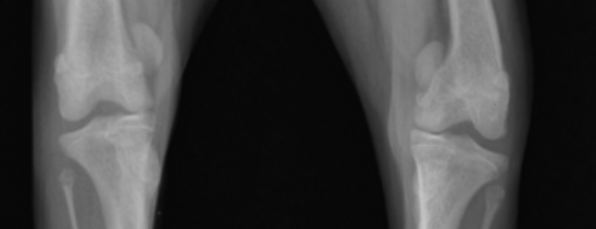

슬개골 탈구는 무릎 관절을 구성하는 슬개골(무릎뼈)이 제 위치에서 벗어나는 질환으로, 진행 단계에 따라 증상이 점차 심해지며 우리 아이의 삶의 질을 크게 떨어뜨릴 수 있습니다.

- 근육 위축: 탈구된 다리에 체중 부하를 하지 않으려 하면서, 해당 뒷다리 근육이 눈에 띄게 위축되는 현상(근위축)이 나타납니다. 다리 굵기가 확연히 차이 날 수 있습니다.

- 다리 변형: 양쪽 뒷다리가 심한 O자 또는 X자 형태로 변형되거나, 무릎이 펴지지 않고 구부러진 상태로 굳어질 수 있습니다.

- 근육 위축 심화: 해당 뒷다리 근육이 매우 심하게 위축되어 다리가 가늘어집니다.